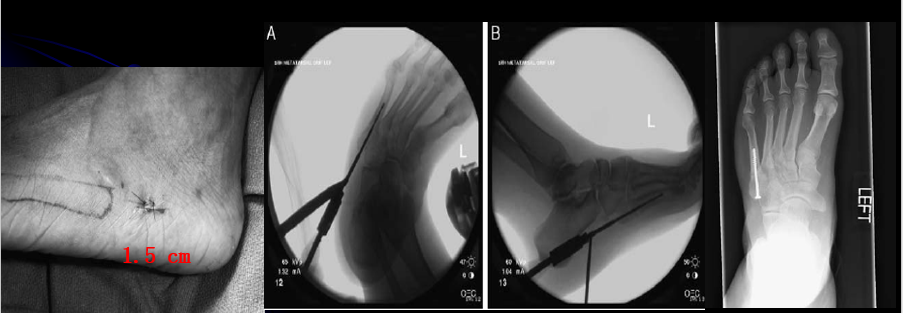

经皮空心钉固定适合于骨折块较大,移位较少,骨质好的患者。具有微创损伤小、不干扰局部的血运、固定牢靠、恢复快等优点。

操作要点:操作要在透视监视下进行,且导针一定要从尖端打入,且在第四、五跖骨间连接以远穿出对侧骨皮质,这样生物力学强度最佳。